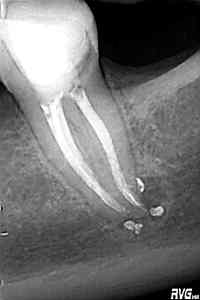

Nos llega a la clínica este 4.5 con necrosis y periodontitis apical. la instrumentación se realizó con técnica de crown-down con limas K3 (SybronEndo) y la obturación con la técnica de ola continua de Buchanan, el tiempo de trabajo (para mi bastante importante) sobre 70-90 min.

Pero no todo se va a dejar al «poder de la irrigación», es muy importante la biomecánica, y la intuición para poder instrumentar esos pequeños conductos laterales que es muchas ocasiones nos dan problemas. Así, pues, os pongo un par de casos que con ayuda de esta «intuición» pudimos hacer un buen tratamiento.

Presentaban un sondaje normal, y sospechamos de que podía tratarse de lesiones por conductos laterales.

Una vez que hemos desbridado biomecánicamente con limas de muy pequeño diámetro, obturamos: